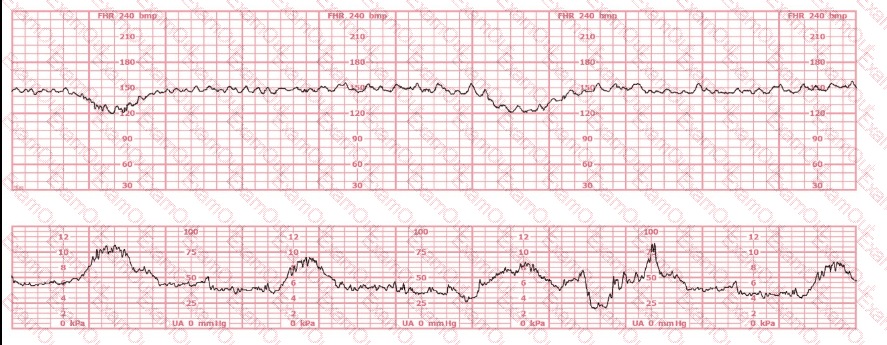

Baseline:

The fetal heart rate baseline is approximately 150 bpm, which is within the normal range of 110–160 bpm.

Variability:

The tracing shows minimal variability (approximately 1–4 bpm amplitude). Minimal variability for a sustained period is categorized as a Category II pattern under NCC/NICHD classification.

Accelerations:

No accelerations are present during the 20-minute representative segment.

Decelerations:

There are no recurrent variable, no recurrent late, and no prolonged decelerations.

Uterine Activity:

The tracing shows very frequent contractions—approximately every 1½ to 2 minutes, which meets the NCC definition of tachysystole when averaged over 10 minutes (more than 5 contractions in 10 minutes).